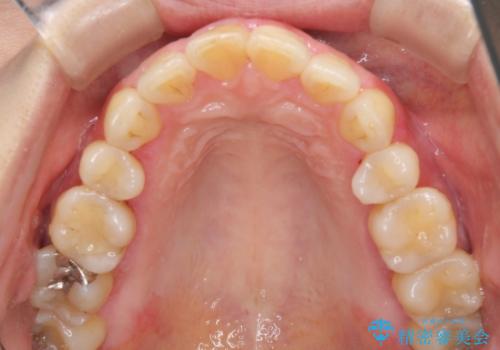

今回は、歯肉炎があるため、その治療を行ってからクラウンを製作しました。

歯肉炎がない場合は、1か月ほどで治療が完了します。逆に、炎症がひどい場合は、治療期間が長くなります。